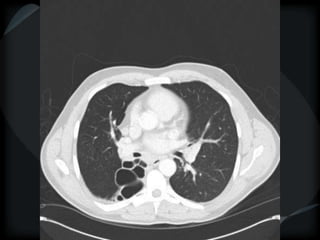

Airspace Patterns

 Perilobular pattern

COP – perilobular pattern